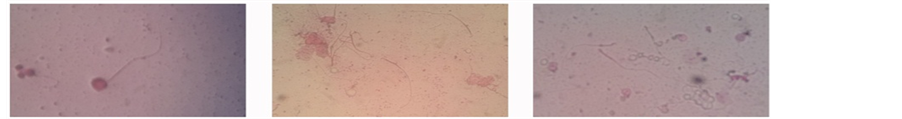

This indicates that plants constitute an important part of the primary healthcare system in developing world [16] . In our study, At the end of the experiment, the obtained sperms shapes were as below: In mice treated with Salvadora persica leaf extract as shown in Figure 1, at concentration 0.5% and 1.0%, normal sperms, while in 1.5%, circular head and short tail. Two tails attached to one head in 2.0%. At 0.5% and 1.0% of mice treated with Moringa pergrina leaf extract exhibited normal sperms whereas ecircular head and short tail obtained in

Figure 1. Observation of sperm shape and size of mice under high power treated with Salvadora persica at different concentrations (40´): (a) Control; (b) 0.5%; (c) 1.0%; (d) 1.5%; (e) & (f) 2.0%.

1.5%. And very long tail and circular head of sperms at 2.0% as it was administrated in Figure 2. In mice treated with Citrullus colocynthis seed extract, the sperms at 0.5% and 1.0 were normal. While at 1.5%, two heads attached to one tail and small, circular head attached to long tail at 2.0% as in Figure 3. The effect was dose dependant, that is the higher the dose the greater the effect. The fact that the extract contained some pro- oxidants like flavonoids, saponnins, anthraquinones, alkaloids and terpenoid suggests that the administration of the extract at higher doses of 100 - 1000 mg/kg body weight for two weeks may lead to oxidative damage due to free radical (FR) and reactive oxygen species (ROS) generation. The defect in sperm morphology detected in mice administered with the extract at higher doses demonstrated that the extract may have direct effect on sexual glands and sperm cells beside it pro-oxidant effect.